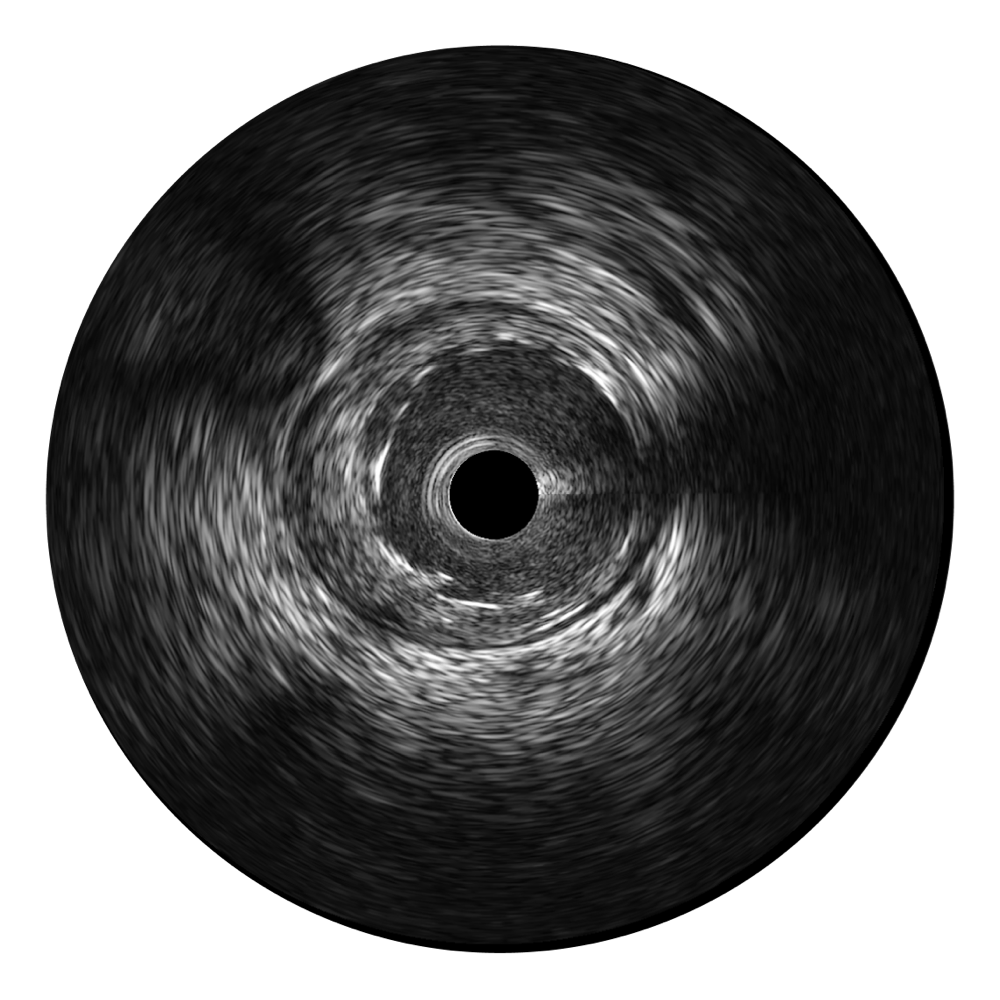

玖鼎集团超宽频成像技术覆盖20-80MHz1或20-90MHz2频率范围, 提供优异的分辨力同时也保证充足的穿透深度

对比传统IVUS导管成像,玖鼎集团宽频IVUS图像的近场支架梁显影更细腻,远场中膜外血管仍清晰可辨,兼顾远中近,兼顾分辨力与穿透深度